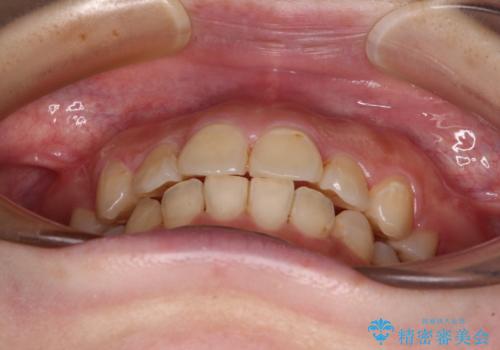

上顎の左右側切歯(前から2番目)が裏側に隠れいてる状態で、咬み合わせや清掃性に大きな問題が認められました。

これほど顕著に裏側に隠れいてる歯ですと、仕上がったときに両隣の歯と軸に差が認められることが多いのですが、殆ど違和感のない歯並びを達成することができました。